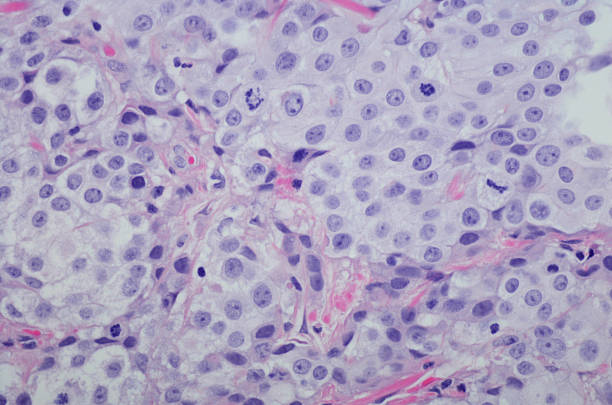

소변에 섞인 혈뇨나 핏물이 나오는 경우

방광암의 초기증상 중 하나로 소변에 섞인 혈뇨나 핏물이 나오는 경우가 있습니다. 방광 내부의 종양이 소변에 혈관을 침범하여 혈뇨가 발생할 수 있습니다. 소변에 섞인 혈뇨나 핏물이 나오는 경우에는 의사를 찾아 상세한 검진을 받아야 합니다. 이러한 혈뇨나 핏물이 지속되는 경우 진단과 치료를 위해 빠른 시일 내에 의료 전문가의 조언을 받아야 합니다.